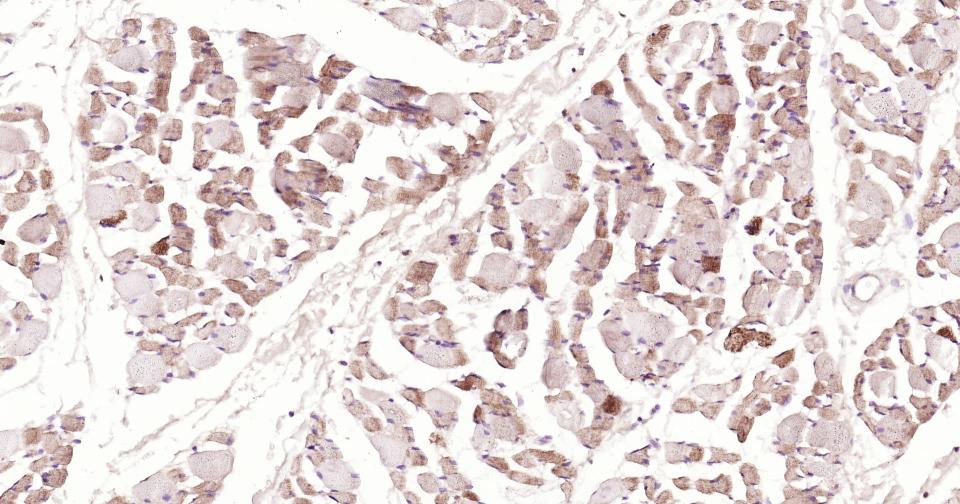

Paraformaldehyde-fixed, paraffin embedded Human Skeletal muscle; Antigen retrieval by boiling in sodium citrate buffer (pH6.0) for 15 min; Antibody incubation with AIF Monoclonal Antibody, Unconjugated(bsm-34316R) at 1:200 overnight at 4°C, followed by conjugation to the SP Kit(Rabbit, SP-0023) and DAB (C-0010) staining.